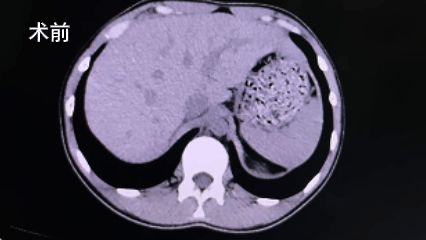

近日,我院外科收治了一位病情复杂的15岁男性患者。该患者因无明显诱因间断出现左侧腰部酸胀不适来院就诊,经详细检查后,被明确诊断为:左侧肾结石伴有积水和感染、左侧输尿管狭窄。

尊重患者家属的意愿,我院外科及手麻科团队随即重新进行严谨的术前评估。患者输尿管存在狭窄段,这使得常规的输尿管软镜和硬镜均无法顺利通过并到达结石部位,取石路径受阻。在必须处理结石的情况下,团队经过充分讨论,将方案聚焦于经皮肾镜碎石取石术。这是临床处理此类复杂肾结石的常用技术之一。

然而,手术的挑战接踵而至。术中,在B超引导下进行穿刺定位时,团队发现患者的结石位于肾的中上盏,目标穿刺点位置偏高。若按常规思路直接穿刺高位目标点进行碎石,存在损伤胸膜的风险,对年仅15岁的患者而言,手术安全性必须放在首位。

面对这一突发问题,手术团队没有退缩,而是迅速转换思路,展现了丰富的临床经验和应变能力。他们果断放弃了高风险的高位穿刺路径,转而选择从较为安全的中下盏进行穿刺建立通道。通道建立后,新的问题又出现了:由于肾积水导致肾盂肾盏扩张变形,肾脏内部结构发生了改变,从新建通道进入的肾镜在向中上盏探寻结石时,因角度和距离问题,仍然无法触及目标结石。手术操作陷入困境,直接强行操作可能造成不必要的损伤。